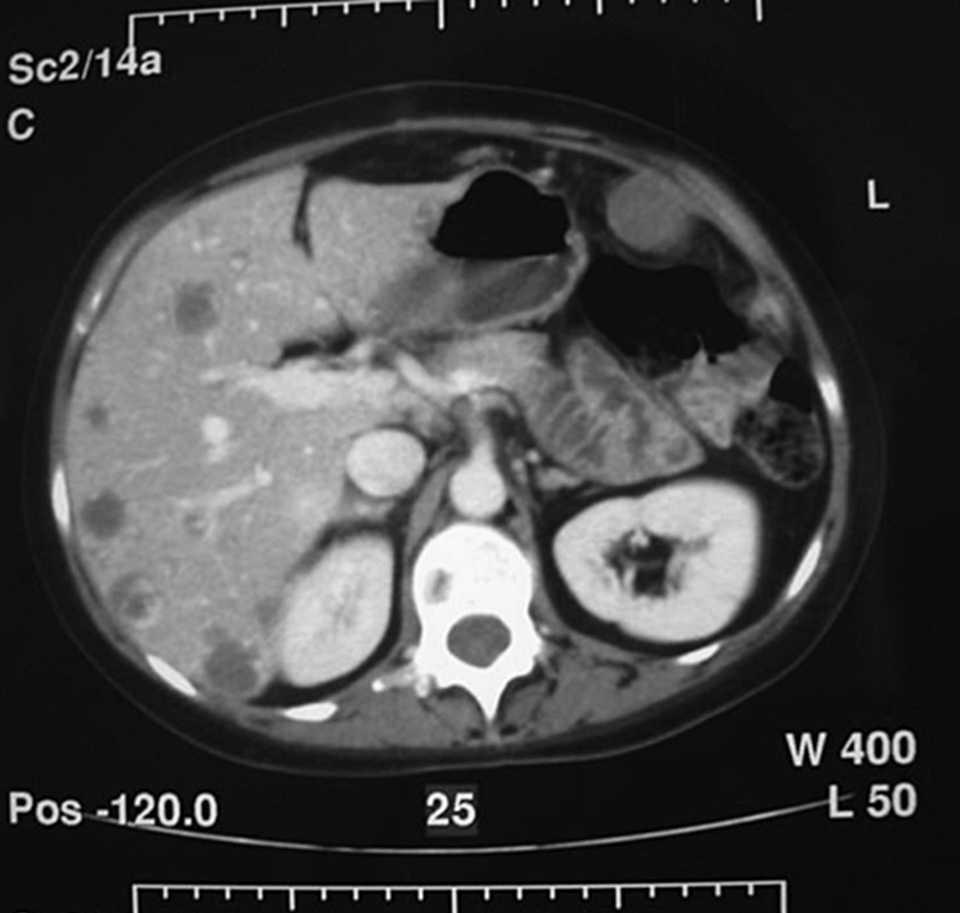

Se practica una ecografía abdominal que informa de abdomen con líquido libre peritoneal compatible con hemoperitoneo. En la tomografía computarizada (TC) abdominal posterior se aprecia una imagen indicativa de infarto esplénico con líquido libre intraperitoneal (fig. 1). Con estos datos clínico-radiológicos se indica la realización de una laparotomía media exploradora de forma urgente, en la que se encuentran 2 l de sangre libre en el abdomen, y tras su aspirado se comprobó un bazo con varias lesiones sangrantes en su superficie que rompían su cápsula; por tanto, se realizó una esplenectomía y colocación de drenaje en el lecho quirúrgico.

Fig.1.Hemoperitoneo con imagen compatible con infarto esplénico en la tomografía computarizada.